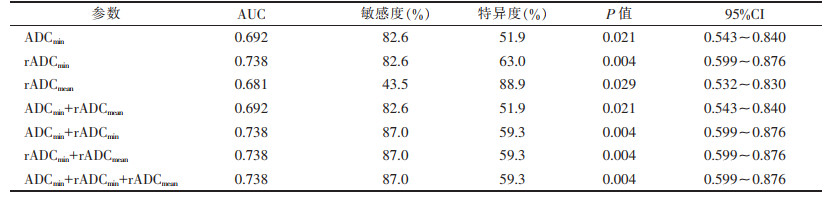

2.3 ADC值对直肠癌区域淋巴结转移的预测效能(表 2)

| 表 2 单一ADC值及多种ADC值联合对直肠腺癌淋巴结转移的预测效能 |

绘制ADCmin、rADCmin、rADCmean预测直肠癌区域淋巴结转移的ROC曲线,得出诊断转移淋巴结最佳界值分别为0.525×10-3 mm2/s、0.410、0.657,其AUC分别为0.692、0.738、0.681(图 3),敏感度为43.5%~82.6%,特异度为51.9%~88.9%。

采用logistic回归分析及ROC曲线分析ADCmin、rADCmin、rADCmean联合对直肠癌淋巴结转移的预测效能,AUC为0.692~0.738(图 4),敏感度为82.6%~87.0%,特异度为51.9%~59.3%。